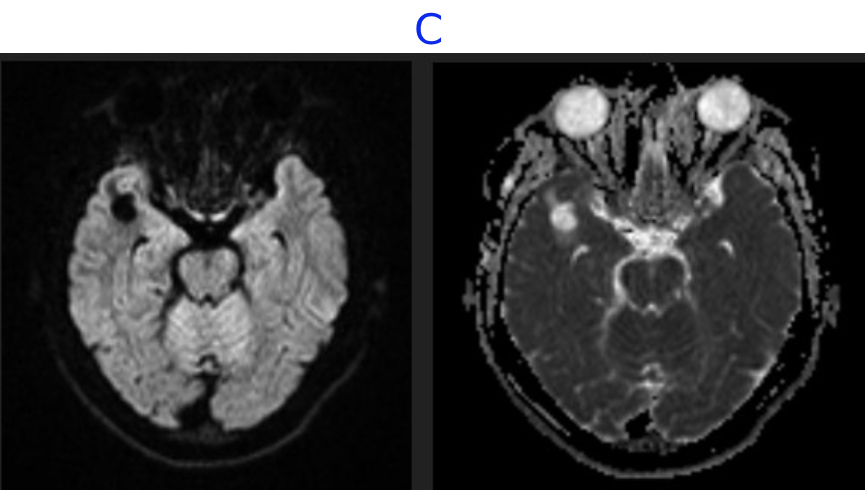

B. FINDINGS - MR BRAIN

• B. FLAIR sequence demonstrates mild perilesional edema in the right anterior temporal lobe.Post contrast T1 demonstrates no enhancement and M2 segment of right MCA indenting the antero-superior pole of the lesion